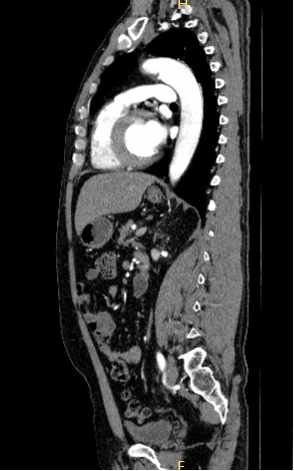

全身各部位血管造影:Incisive CT可以轻松实现大范围CT血管造影(CTA),准确了解血管及相关脏器的形态结构,评估血管及脏器功能,准确判断出血,栓塞、血管瘤、血管畸形、狭窄及肿瘤供血情况,为临床治疗提供极大帮助。

▲ 胸腹部CTA-主动脉夹层一目了然